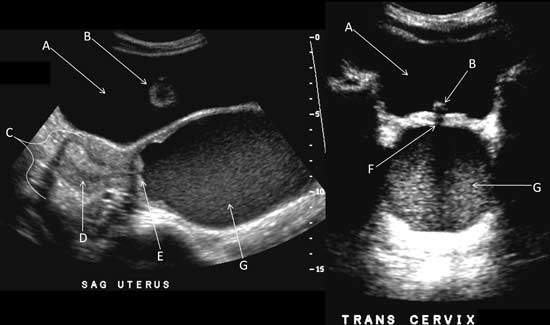

Transabdominal sagital and transverse images of the pelvis demonstrating hematometrocolpos:

A: Bladder

B: Foley Catheter

C: Uterus

D: Endometrium

E: Cervical Os

F: Urethra

G: Blood filled vagina